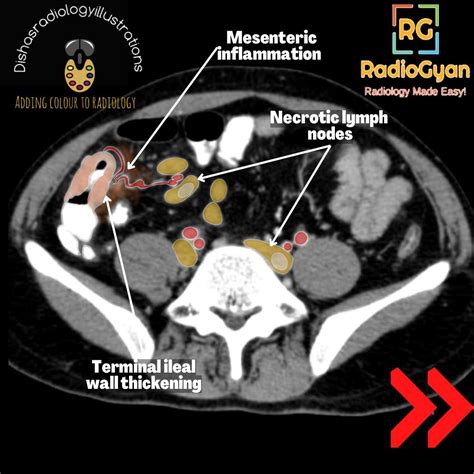

The visual and physical characteristics of these nodes often change significantly. They may feel hard, fixed, or conversely, fluctuant (soft/fluid-filled) if the necrosis has led to abscess formation. Imaging studies, such as CT scans or MRI, are the standard tools for identifying these nodes, as they show specific patterns of contrast enhancement that distinguish necrotic tissue from healthy or inflamed tissue.

• Metastatic Cancer: When cancer spreads from an organ to a lymph node, it grows rapidly. Eventually, the tumor cells may outgrow their blood supply, leading to central necrosis within the node. This is common in squamous cell carcinomas.

CT/MRI Scan To identify the location and characterize the "ring enhancement" typical of necrotic nodes.

• Necrotic Lymph Node CT